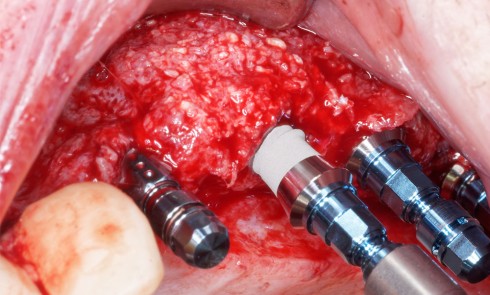

Les empreintes sont validées par le praticien. Elles sont nettoyées et désinfectées, si possible au cabinet dentaire. Trop nombreux sont encore les praticiens qui adressent au laboratoire des empreintes souillées de salive ou de sang, ce qui est un manque de considération pour leur partenaire de laboratoire [1].